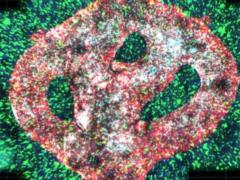

Вирус папилломы человека может быть гораздо опаснее, чем считалось до этого. Предполагалось, что вирус, известный как бета-ВПЧ, в редких случаях вызывает рак кожи, усиливая действие ультрафиолета. Но новое исследование показало, что он может захватывать клетки кожи и напрямую вызывать развитие рака, сообщает Science Alert.

Генетический анализ показал нечто неожиданное: бета-ВПЧ фактически интегрировался в ДНК опухоли женщины, где он продуцировал вирусные белки, способствующие развитию рака.

До этого ученые не обнаруживали свидетельств того, что бета-ВПЧ может интегрироваться в клеточную ДНК, и того, что он может активно поддерживать раковую опухоль.